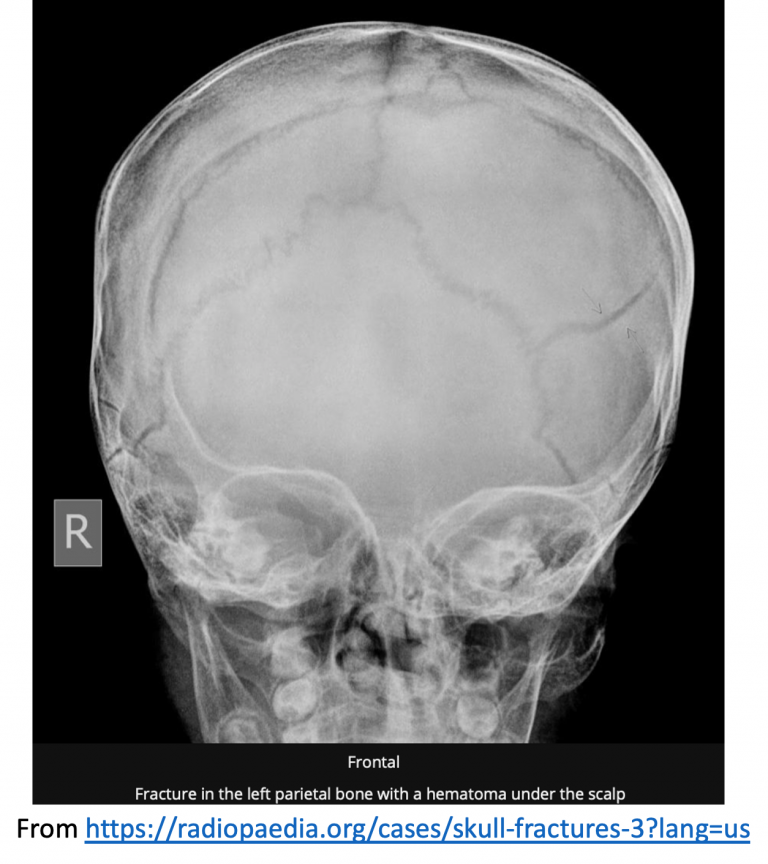

From radiopaedia.org

Skull fracture (linear) Image What Is A Hinge Skull Fracture — learn about the causes, symptoms, diagnosis, and treatment of skull fractures, which are breaks in one or more. Learn about the different types of skull fractures, including. — a basilar skull fracture is a type of traumatic head injury that involves a break in one or more bones at the base of the skull. A depressed fracture. What Is A Hinge Skull Fracture.